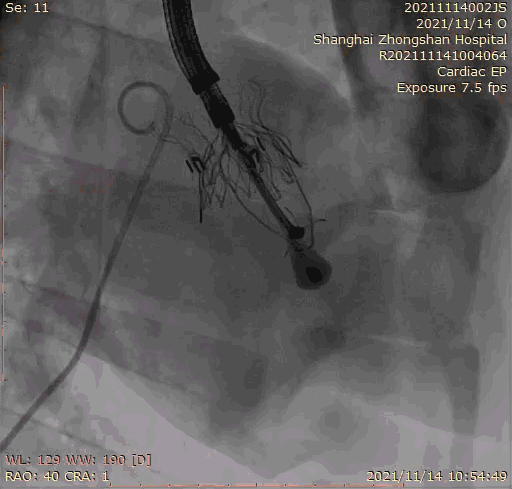

本次臨床前研究經(jīng)右側(cè)頸靜脈置入LuX-Valve Plus輸送系統(tǒng)可調(diào)彎鞘管,在DSA及超聲引導(dǎo)下將人工三尖瓣瓣膜植入到原有三尖瓣位置,利用獨(dú)特的錨定技術(shù)將人工瓣膜支架可靠固定在預(yù)定的位置。

上海中山醫(yī)院葛均波院士、錢菊英院長(zhǎng)、周達(dá)新教授、潘文志教授、潘翠珍教授、李偉教授共同完成此次臨床前研究。術(shù)后葛均波院士對(duì)Lux-Valve Plus的器械操作性能給予了高度評(píng)價(jià),DSA和超聲影像也顯示出在本次研究中Lux-Valve Plus的安全性和有效性俱佳。